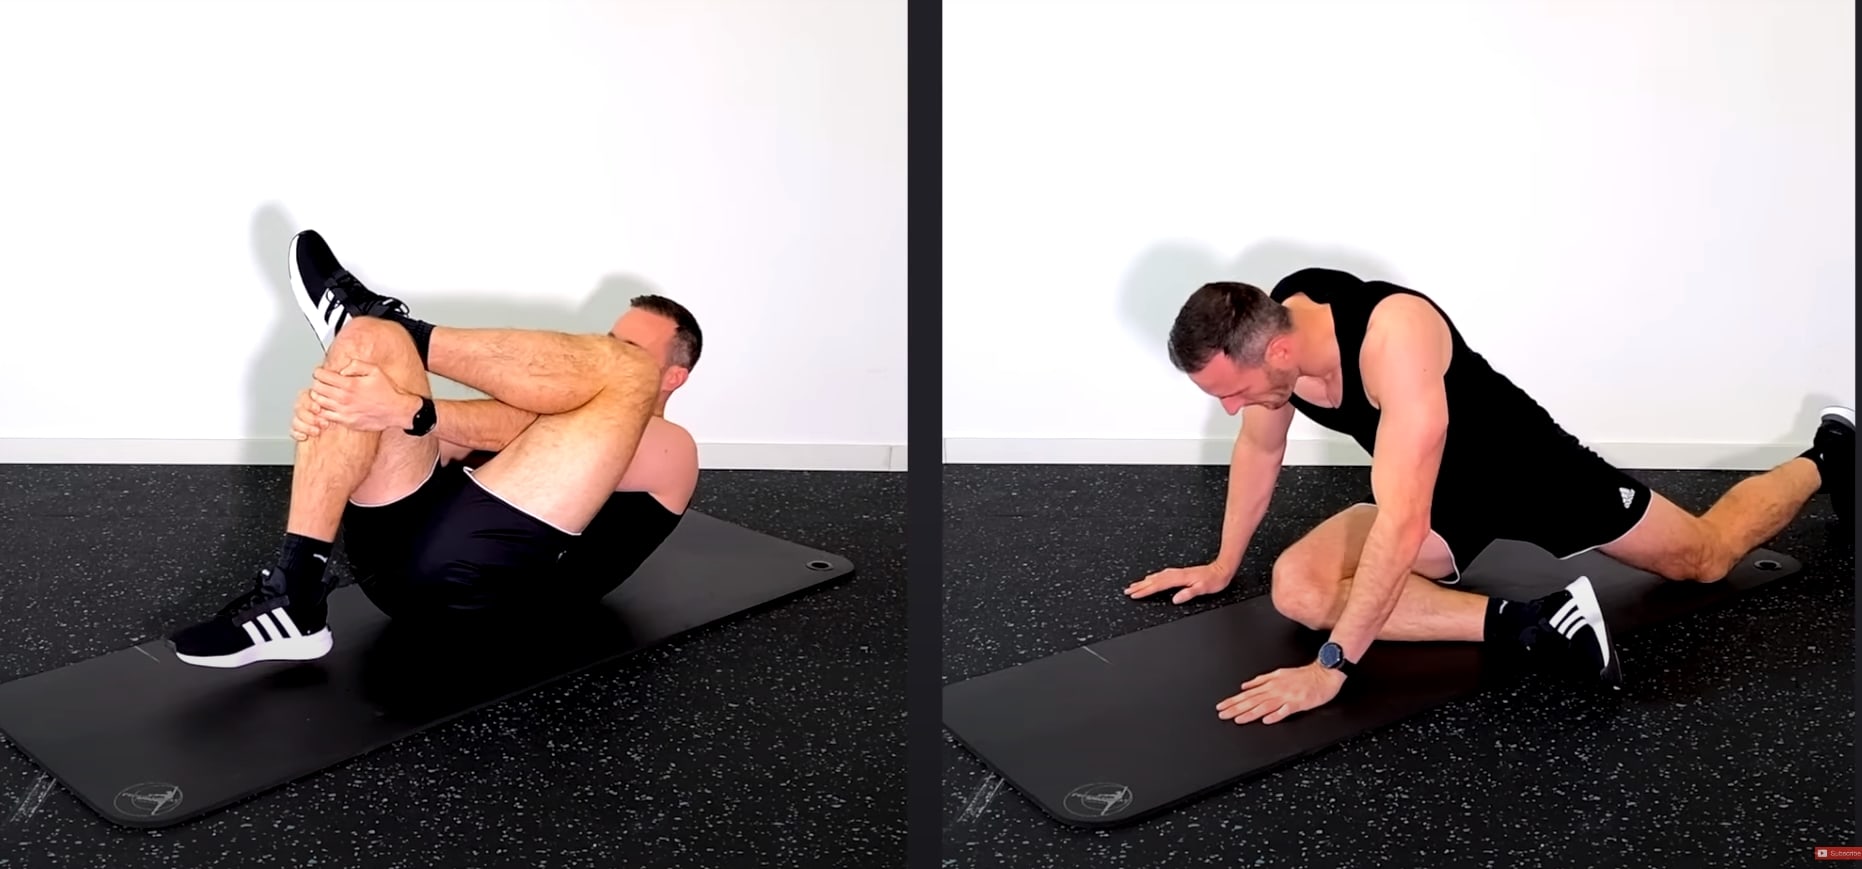

Ett annat kortsiktigt alternativ är att stretcha de djupa glutealmusklerna. Här är 2 stretchar som du kanske vill prova hemma:

- Standard piriformis-stretch i sittande eller liggande

- Yoga-pose